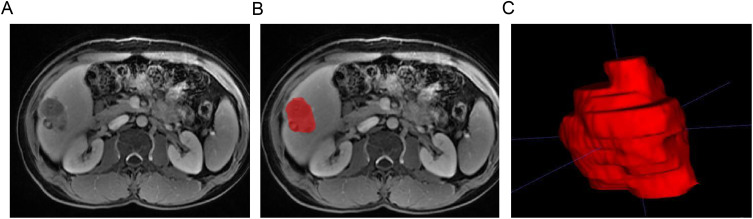

Patients and methods: Clinical and magnetic resonance imaging (MRI) data of 131 patients (48 with TACE refractoriness) who underwent repeated TACE treatment for HCC were retrospectively collected. The training and validation cohorts comprised 104 and 27 cases, respectively, following an 8:2 ratio. Clinical imaging characteristics related to TACE refractoriness were identified through logistic regression analysis. HCC lesions on arterial phase, portal phase, delayed phase, and T2-weighted fat suppression MRI images before the first TACE were manually delineated as regions of interest. Dimension reduction was conducted using variance threshold, univariate selection, and least absolute shrinkage and selection operator methods. Relevant indices of TACE refractoriness were selected. ML algorithms, including a support vector machine, random forest, logistic regression and adaptive boosting, were used to construct the radiomics, clinical prediction, and combined models. The predictive performance of these models was evaluated using receiver operating characteristic curves. The optimal model was presented as a nomogram and verified through calibration and decision curve analyses.